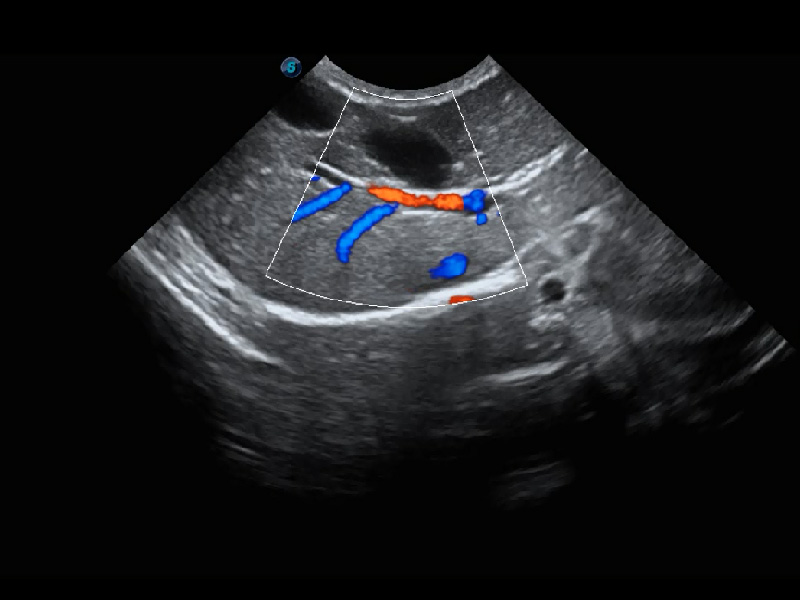

ProPet 60 作為一款高端臺式動物超聲設(shè)備,為動物醫(yī)生的日常診斷提供了一系列貼合動物臨床需求、解決臨床實(shí)際問題的高級成像功能。憑借全系列高清探頭,滿足醫(yī)生對腹部、心臟、生殖、淺表、肌骨等成像的所有需求,切實(shí)幫助您提升檢查效率,提高診斷信心。